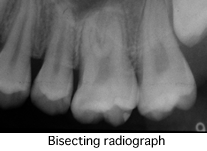

What is panorama?